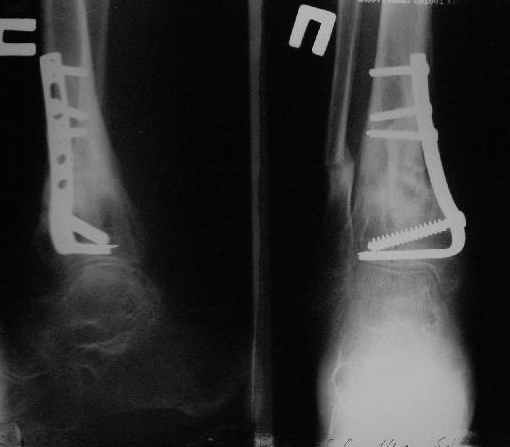

Нашел в комп-ре схожий случай:

1) з/репозиция, 2) фиксация 2 спицами, 3) аппарат, 4) фиксационные

спицы удалены...

См. аттачт.

А можно было наложить аппарат и по поводу ложного сустава...

По крайней мере не было бы укорочения (пусть и в 2 см)...